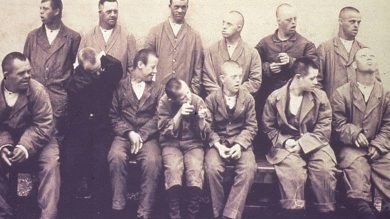

Vipeholm Deneyleri: Dişlerin Nasıl Çürüdüğünü Anlamamızı Sağlayan Ürkütücü Bir Çalışma

1940’lı ve 1950’li yıllarda yapılan bir dizi deney, şeker ile diş çürüğü arasındaki ilişkiye dair önemli kanıtlar ortaya koydu. Vipeholm…